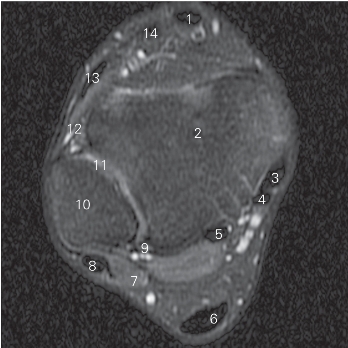

图5-36 经远侧胫腓关节的横断层 MR T2WI FS

1 胫骨前肌 tibialis anterior 2 胫骨 tibia

3 胫骨后肌 tibialis posterior

4 趾长屈肌 flexor digitorum longus

5

长屈肌 flexor hallucis longus 6 跟腱 tendo calcaneus

7 腓骨短肌 peroneus brevis 8 腓骨长肌 peroneus longus

9 下胫腓后韧带 posterior lower tibiofibular ligament

10 腓骨 fibula

11 胫腓远侧关节 distal tibiofibular joint

12 下胫腓前韧带 anterior lower tibiofibular ligament

13 趾长伸肌 extensor digitorum longus

14

长伸肌 extensor hallucis longus